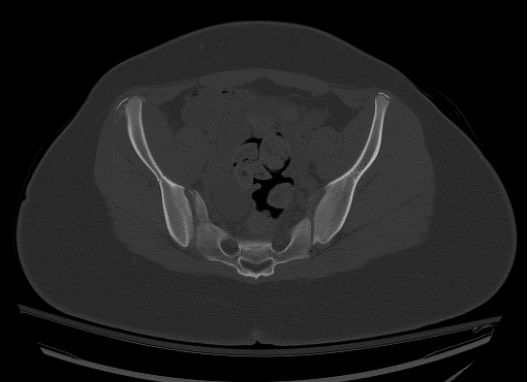

What injury could be related to this anterior superior iliac spine avulsion injury? What's your diagnosis?

What is your diagnosis?